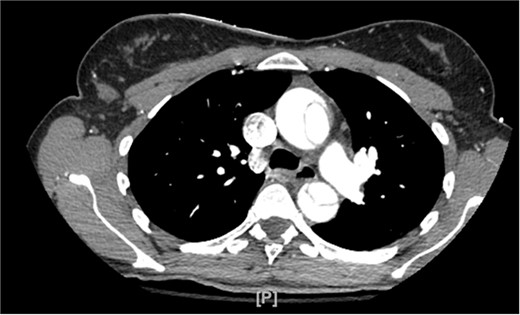

A 48-year-old female patient with no past medical history presented for the evaluation of sudden-onset chest pain. An electrocardiogram was performed, revealing ST segment elevation in the aVR lead and diffuse ST segment depressions in the anterolateral leads. During coronary angiography, the left and right main coronary arteries were unable to be engaged. An aortogram was then conducted, which raised concern for an aortic dissection as a false lumen was identified. The procedure was aborted and a computed tomography angiogram (CTA) was obtained that showed a type A aortic dissection along with aneurysmal dilatation of the ascending thoracic aorta (Fig. 1). Cardiothoracic surgery then took the patient emergently to the operating room.

CTA demonstrating type A aortic dissection, with false lumen present in both the ascending and descending portions of the aorta.